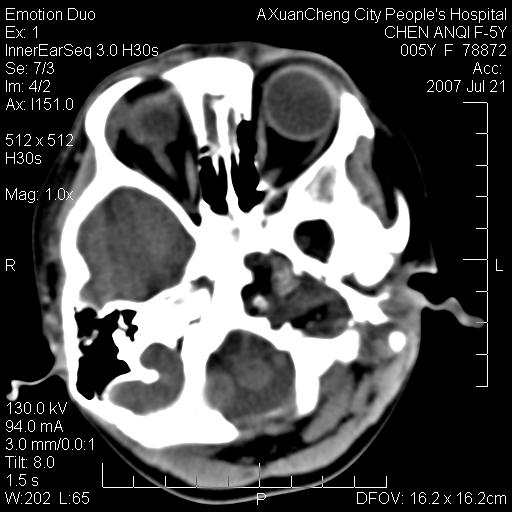

患儿5岁,左耳流脓痛疼一周,左外耳道肉芽组织填塞 软组织窗显示病灶内结节状低密度影为气体密度

左侧中耳炎并胆脂瘤,左颞骨岩部骨质破坏并颅内感染积气。

考虑化脓性中耳乳突炎伴胆脂肪瘤形成并左颞叶感染,不除外合并嗜酸性肉芽肿.

考虑化脓性中耳乳突炎伴胆脂瘤形成合并左颞叶感染,不除外伴嗜酸性肉芽肿.